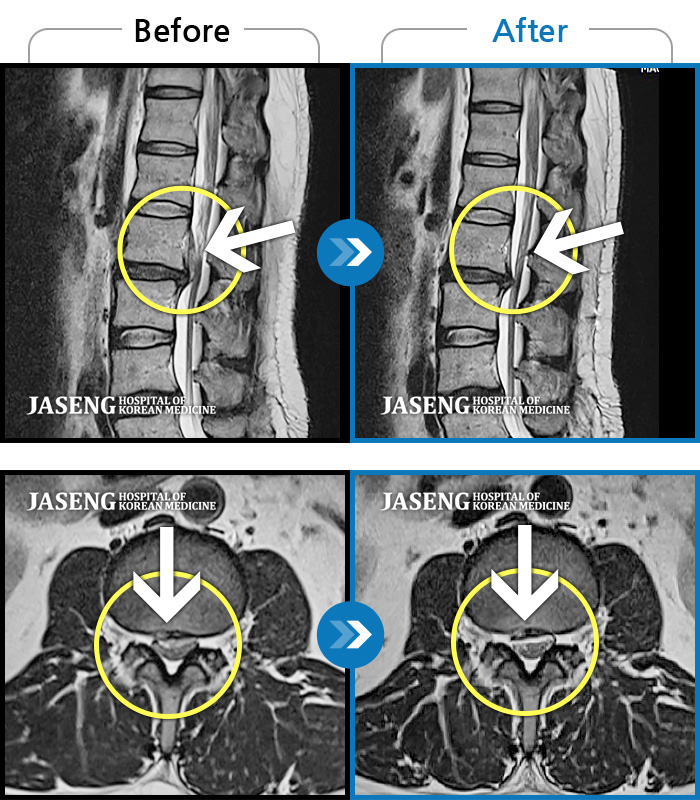

컴퓨터 모니터로 많이 튀어나온 디스크도 쑥 들어간 mri사진 사례들을 여러개 보여주시며 이보다 더 많은 사례가 있다고 제게 희망을 주셨습니다